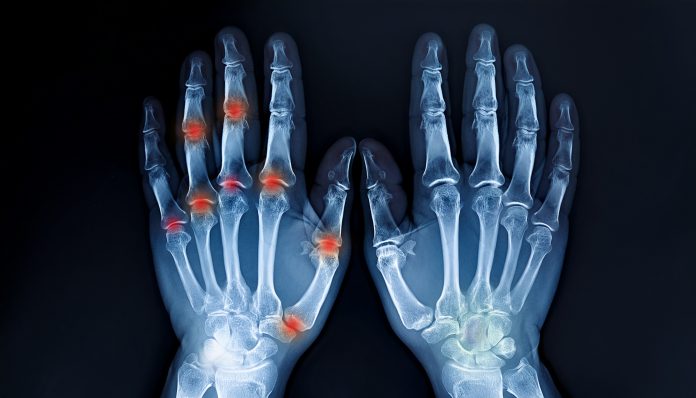

Žena iz Cazina već godinama pati od bolova u zglobovima, trnjenja ruku i noćnih grčeva.

Zbog tih problema nije mogla normalno spavati, a ujutro bi se budila sa ukočenim rukama, ne mogavši ih pomaknuti ili obavljati jednostavne svakodnevne zadatke. Lijekovi koje je koristila samo su na kratko smanjivali bolove, ali nikad nije osjećala pravi napredak. Ipak, u trenutku kad je već izgubila nadu, odlučila je poslušati savjet jedne starije žene iz komšiluka i probati prirodni recept koji je došao iz narodne medicine.